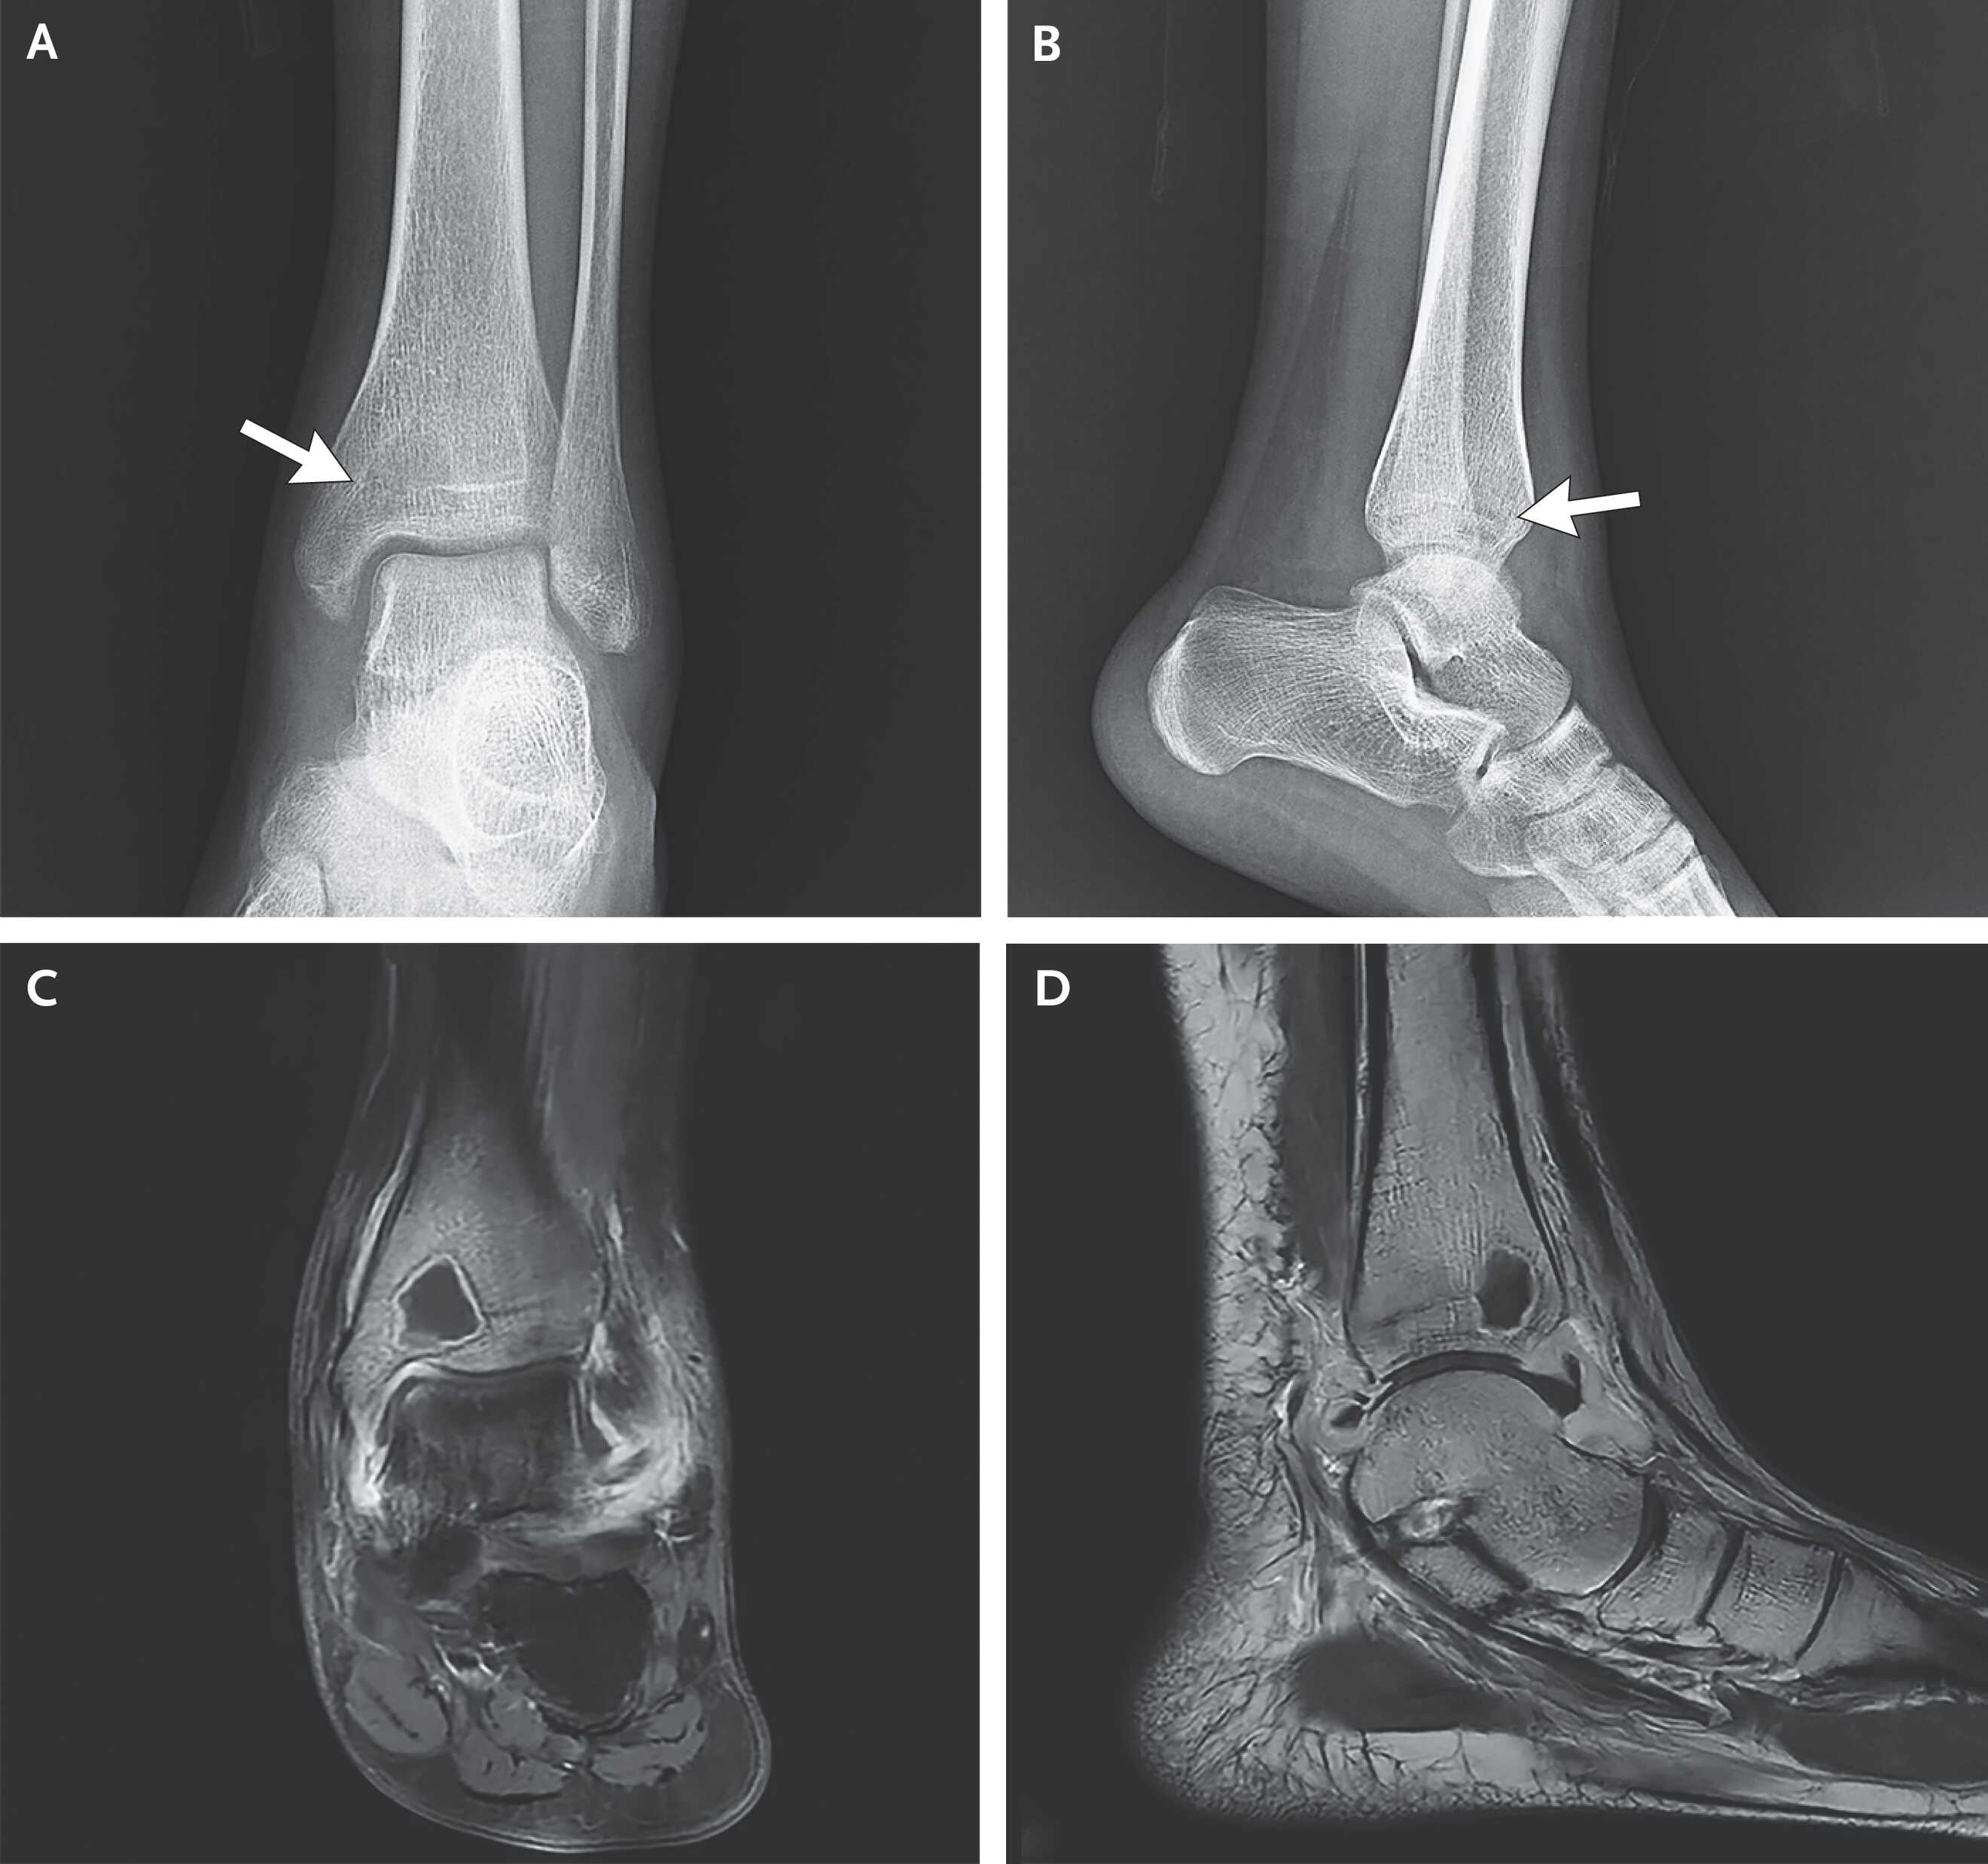

При осмотре определялась чувствительность при пальпации левой лодыжки и ограничение активного и пассивного объема движений в ней. На рентгенограмме было видно рентгенопрозрачное образование с нечеткими краями, перекрывающее зону роста в дистальной части большеберцовой кости, а также отек мягких тканей без признаков перелома или реакции надкостницы. Врачи Хайцзянь Ли (Haijian Li) и Пей Хань (Pei Han) из аффилированной с Шанхайским университетом Цзяотун Шестой народной больницы Шанхая поделились этим случаем в The New England Journal of Medicine.

На МРТ левой ноги в дистальной части большеберцовой кости визуализировалось гипоинтенсивное образование размером 14 × 16 × 12 миллиметров с гиперинтенсивным склеротическим ободком. Эта картина, известная как симптом пенумбры, специфична для подострого остеомиелита. На основании данных обследования девушке поставили диагноз внутрикостного абсцесса (абсцесса Броди) на почве подострого остеомиелита. Ей выполнили хирургическую обработку абсцесса и назначили курс антибиотикотерапии.